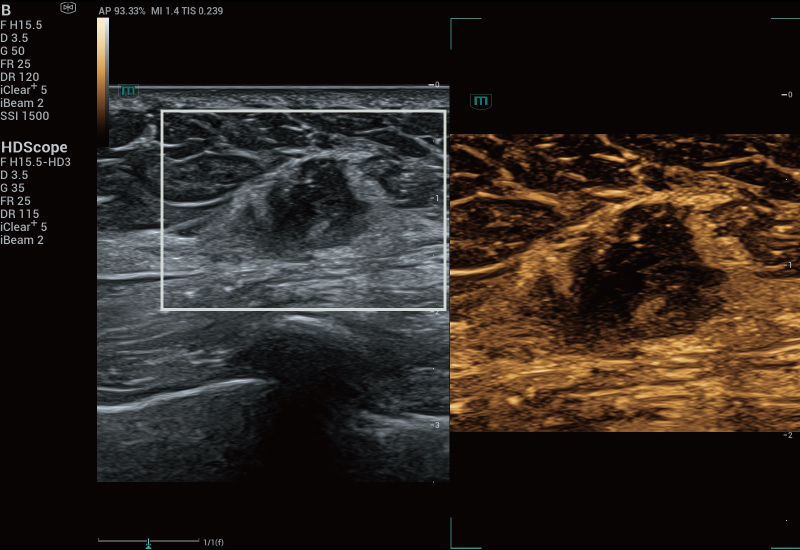

STVi enables the quantitative evaluation of tissue viscosity and

provides real-time multi-parameter imaging, offering a more

comprehensive approach to imaging diagnosis and quantitative

analysis of chronic liver diseases, breast lesions, and other

conditions.

Dual quantitative coefficients

Chronic liver disease assessment

Multiple quantification tools

Breast tumor assessment